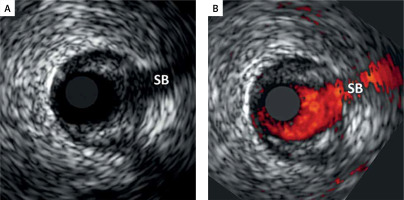

Figure 1

Schematic presentation of key components of the atherosclerotic plaque in relation to their architecture and plaque rupture risk [24, 25]. Today, these components can be quantified in vivo with virtual histology (VH-IVUS) using a recently validated novel VH-IVUS algorithm – quantitative virtual histology, qVH [21]. Color-coding is consistent with the VH-IVUS tissue map representation (fibrous tissue – green, necrotic core – red, calcium – white, fibro-fatty – yellow). A – fibrous cap thickness, B – necrotic core area and thickness, C – necrotic core angle. For a typical example of measurements performed in this study see Figure 3